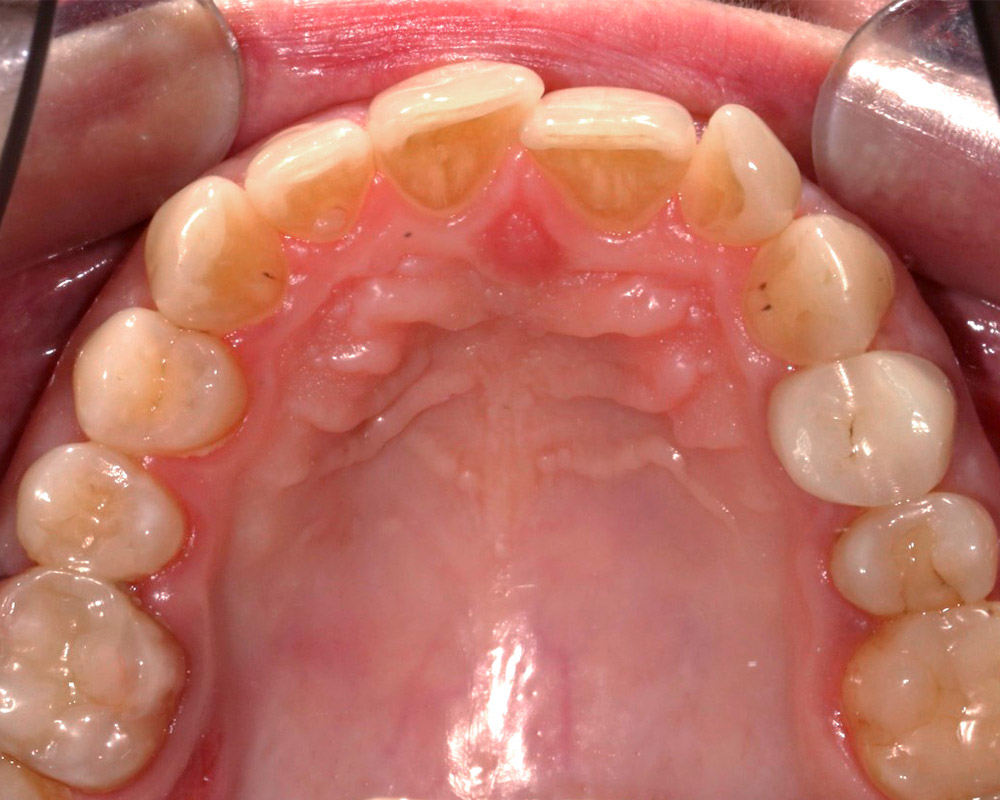

Кейс 21

ДО

ПОСЛЕ